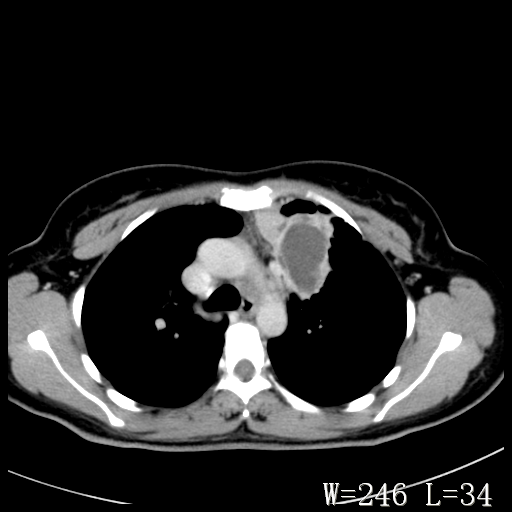

标题: CT27017:1、肺结核?2、永存左上腔静脉。

女,32岁,自述肺结核治疗多年复查。

1)考虑左肺上叶肺脓肿,节段性肺不张。2)永存左上腔静脉。

1)考虑左肺上叶节段性肺不张。原因?2)永存左上腔静脉。

考虑左肺上叶胸腺瘤可能性大。肺不张/永存左上腔静脉

胸骨后偏左侧囊实性病灶,考虑胸腺瘤可能性大.

1、胸骨后偏左侧囊实性病灶,考虑胸腺瘤可能性大。2、永存左上腔静脉。